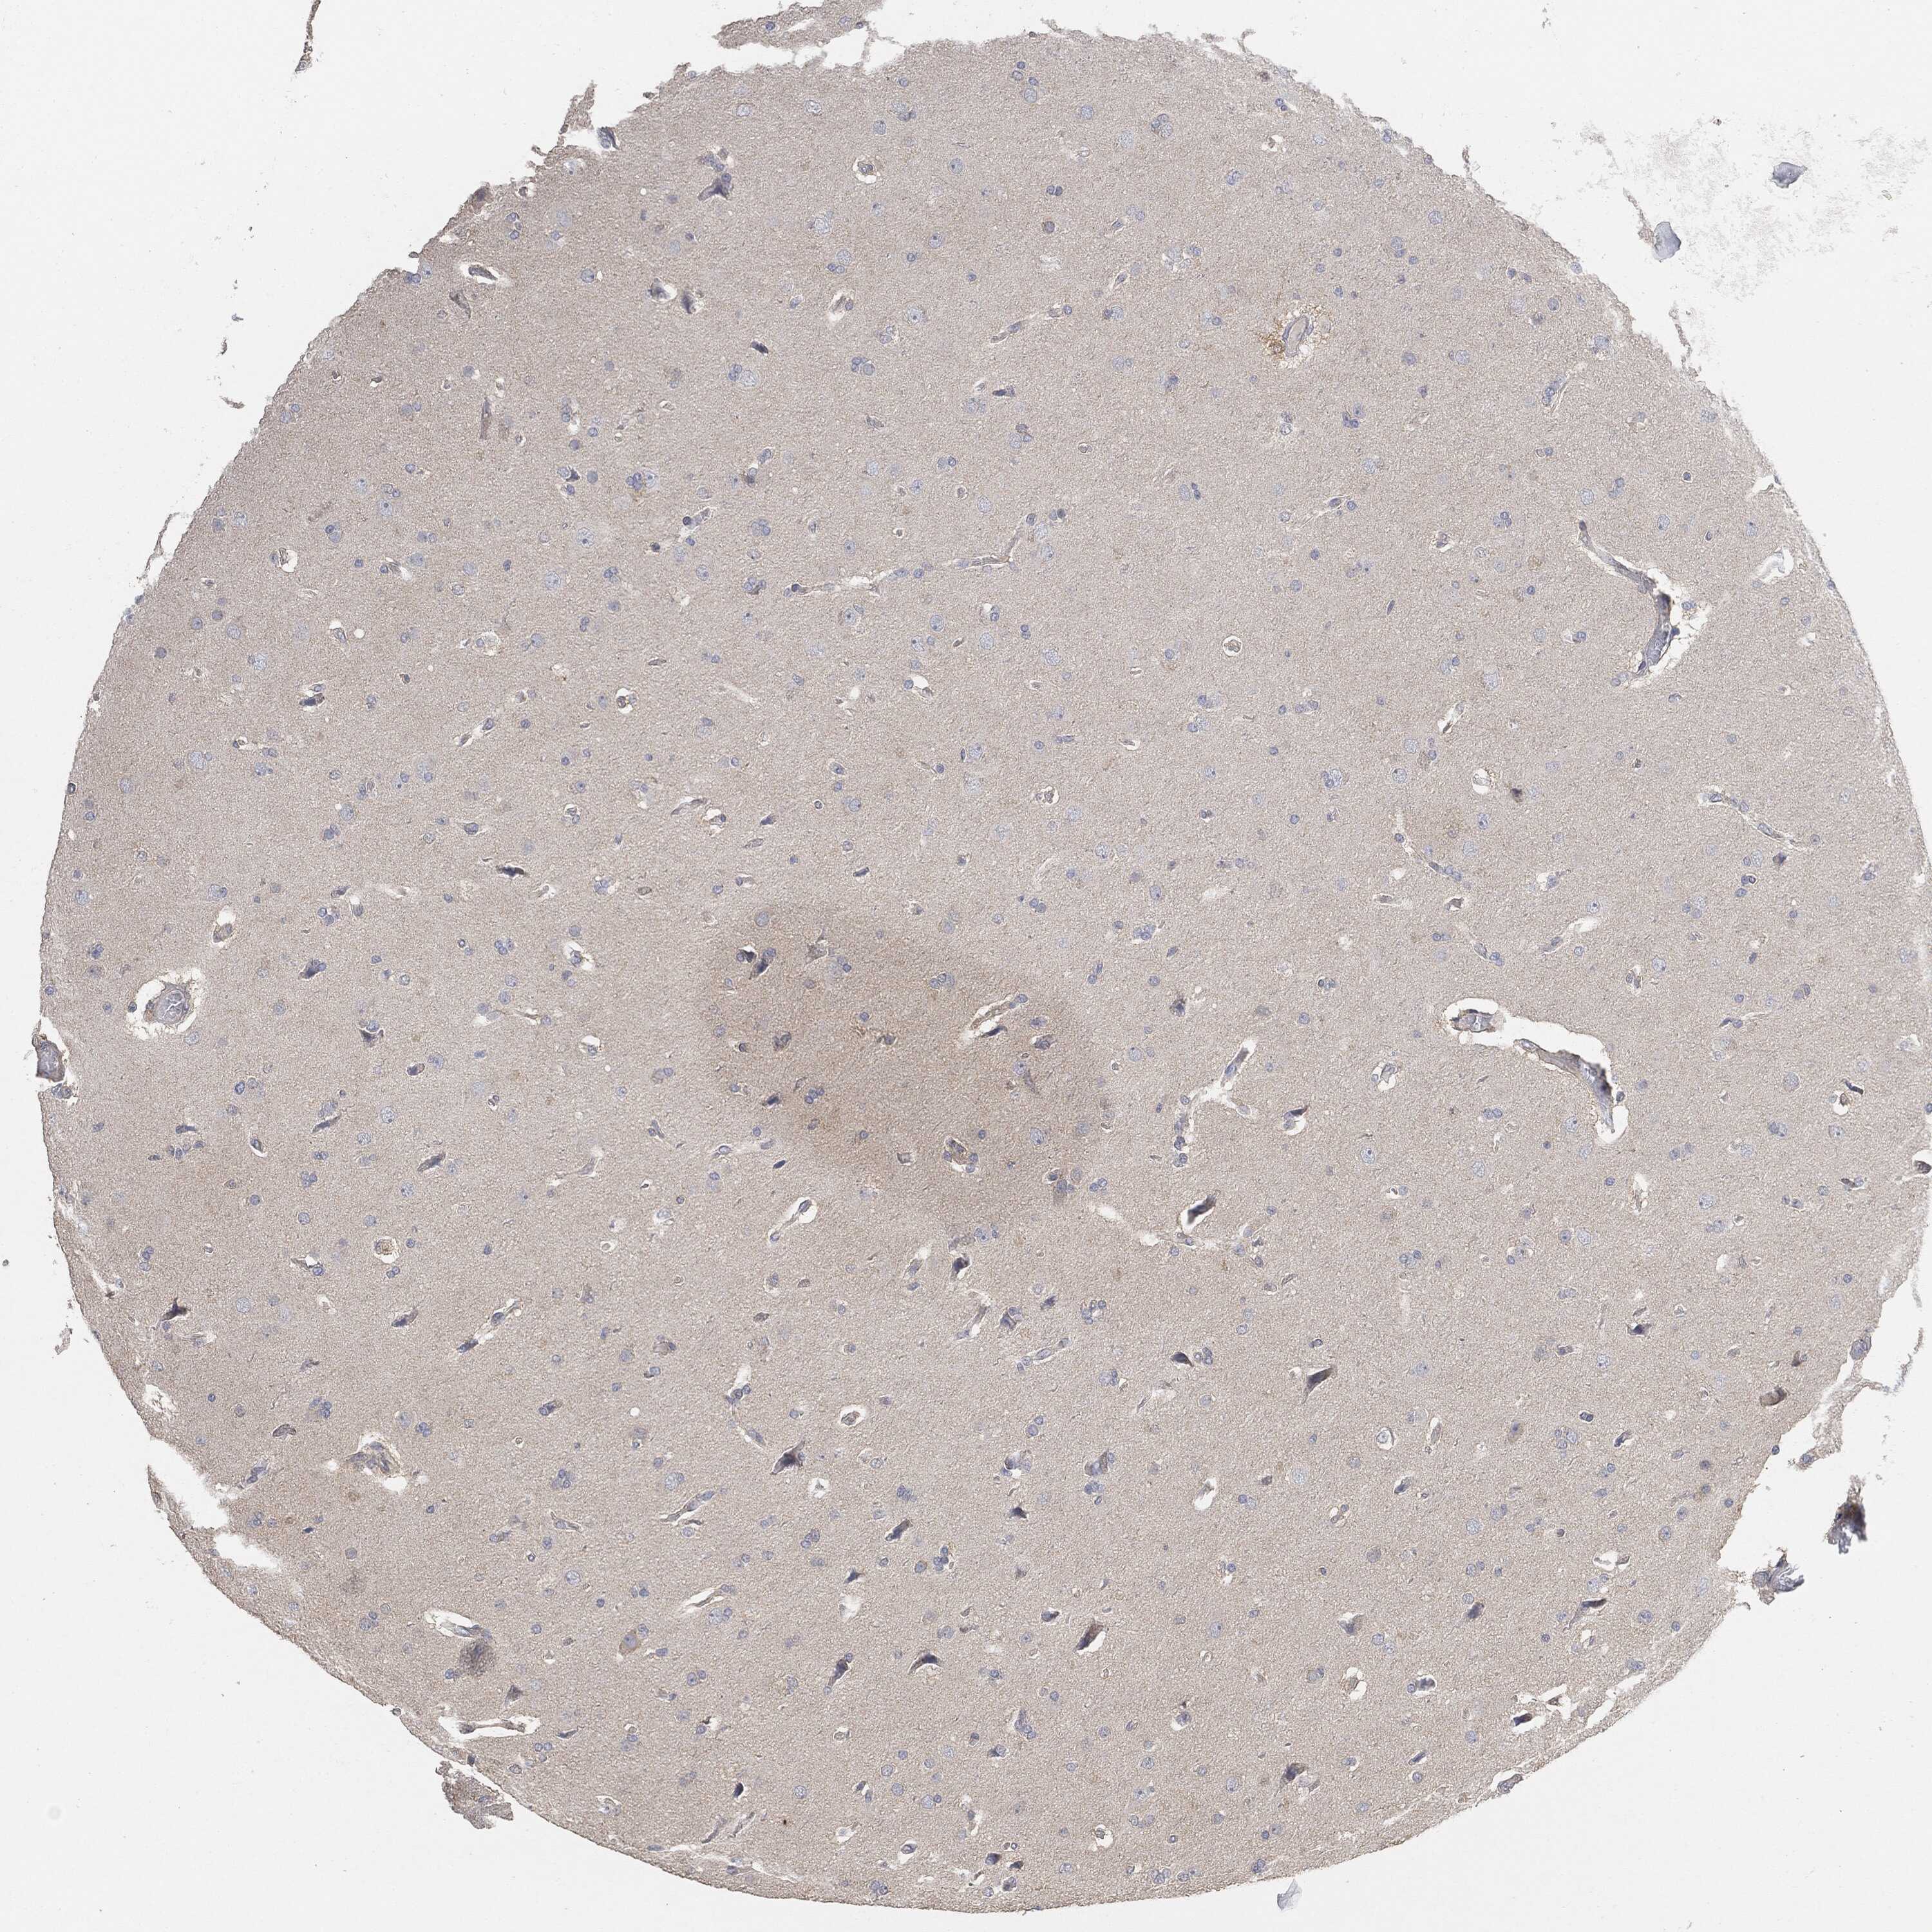

GLIOMA - Protein expressioni

A mouse-over function shows sample information and annotation data. Click on an image to view it in a full screen mode. Samples can be filtered based on level of antibody staining by selecting one or several of the following categories: high, medium, low and not detected. The assay and annotation is described here.

Note that samples used for immunohistochemistry by the Human Protein Atlas do not correspond to samples in the TCGA dataset.

Antibody stainingi

Antibody staining in the annotated cell types in the current human tissue is reported as not detected, low, medium, or high, based on conventional immunohistochemistry profiling in selected tissues. This score is based on the combination of the staining intensity and fraction of stained cells.

Each image is clickable and will lead to virtual microscopy that enables deeper exploration of all samples and also displays staining intensity scores, fraction scores and subcellular localization as well as patient and tissue information for each sample.

Glioma, malignant, High grade

Glioma, malignant, Low grade

Glioma, malignant, NOS